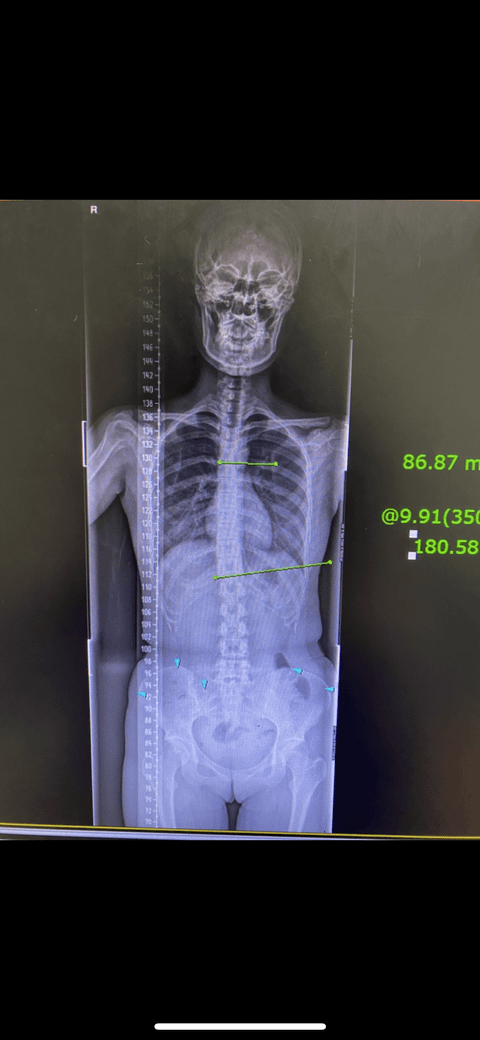

현 25살 여성이고 20년도 9월에 혹여 척추측만일까 찍어본 엑스레인데 의사가 몇도정도휘었다 측만은아니랫거든요 찾아보니 10도이상휘면 측만이라길래 사진상 몇도휘었는지 알수있을까요?

상기 오른쪽 연두색이 두 척추각이 이루는 각을 측정한 것으로 9도정도 휘어있습니다.

9도라고 측정이 되어있네요

각도기를 통해 확인해 보면 알 수 있듯이 3-5 도 정도 기울어 진 것으로 보이며 이는 척추측만증에 해당하지는

않는 것으로 보입니다. 그러나 이후 자세 교정을 하지 않고 나이가 들수록 각도는 더 진행할 수 있어 평소 스트레칭을

통해 척추를 곧게 유지하고 짝다리를 집고 있거나 책상 다리로 앉아 허리를 구부리는 것을 피하는 것이 좋을 것으로

보입니다. 감사합니다.

사진 해상도가 좋지 않아 정확히 측정은 불가능합니다.

엑스레이 사진에 선을 그어서 각도를 측정해야 합니다. Cobb's angle이라고 하고 위의 사진은 측정해보지 않아도 한눈에 큰 이상이 없음을 알 수 있습니다.

특발성 척추측만증 (특별한 원인 없는 척추측만증)은 25도 미만의 경우 경과관찰하는 경우가 많고 25도 이상부터 보조시 착용을 고려, 45도 이상부터 수술을 고려합니다.

척추측만증은 성장기에 주로 진행하고 심해지므로 현재 25세 이신 작성자분은 척추측만증이 심해질 가능성이 굉장히 낮습니다. 걱정하지 않으셔도 되겠습니다.